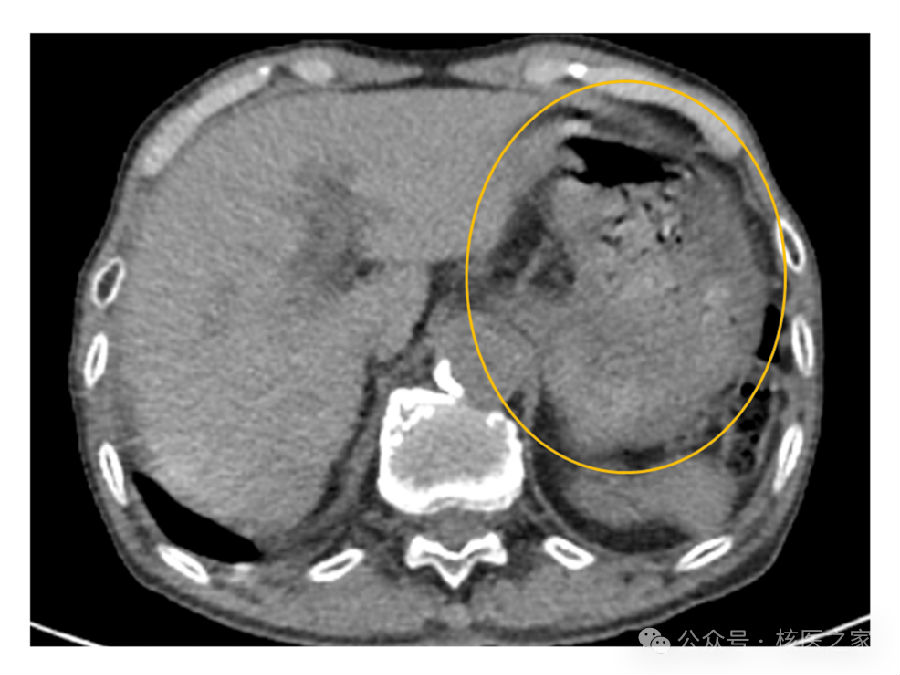

患者无糖尿病史,无肌肉相关症状,亦无包括肌炎在内的结缔组织病。同时,检查当日及前一日均未进行运动。胃内容物充盈明显(图2),提示其在检查前可能进食。尽管患者自述空腹,但考虑其高龄,可能遗忘了禁食要求。

图2.大量胃内容物